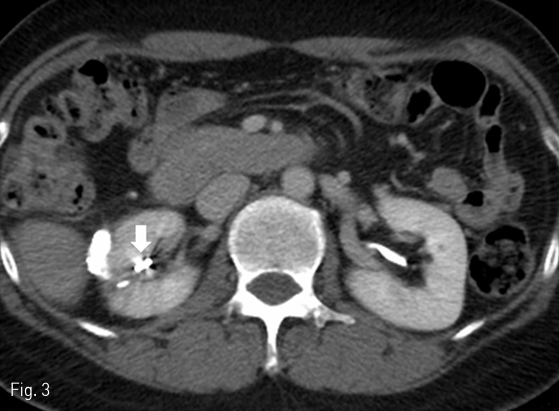

경피적 색전술 후 환자 증상 호전되었으며, 약 15개 월 후 외래 경과 관찰하면서 시행한 조영증강 복부 전산화 단층촬영에서 urinoma는 소실되었고 fistulous tract은 coil에 의해 compact occlusion되어있음을 확인하였다(Fig. 3).

Fig 3

Regular follow-up contrast enhanced CT in 15 months later demonstrates the compact occlusion of the urinary fistulous tract by coils (arrow) without recurred urinoma.